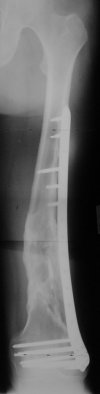

Attached are few examples from our Hospital:

Malpositioning is much too common (recurvatum, varus - valgus).

B. Fixation loosening: distal cutting of the nail, non-unions do happen (cases attached).

Locking Plating has more distal screws than any nail, fixed angles and provides much better fixation, especially in osteoporotic bone.